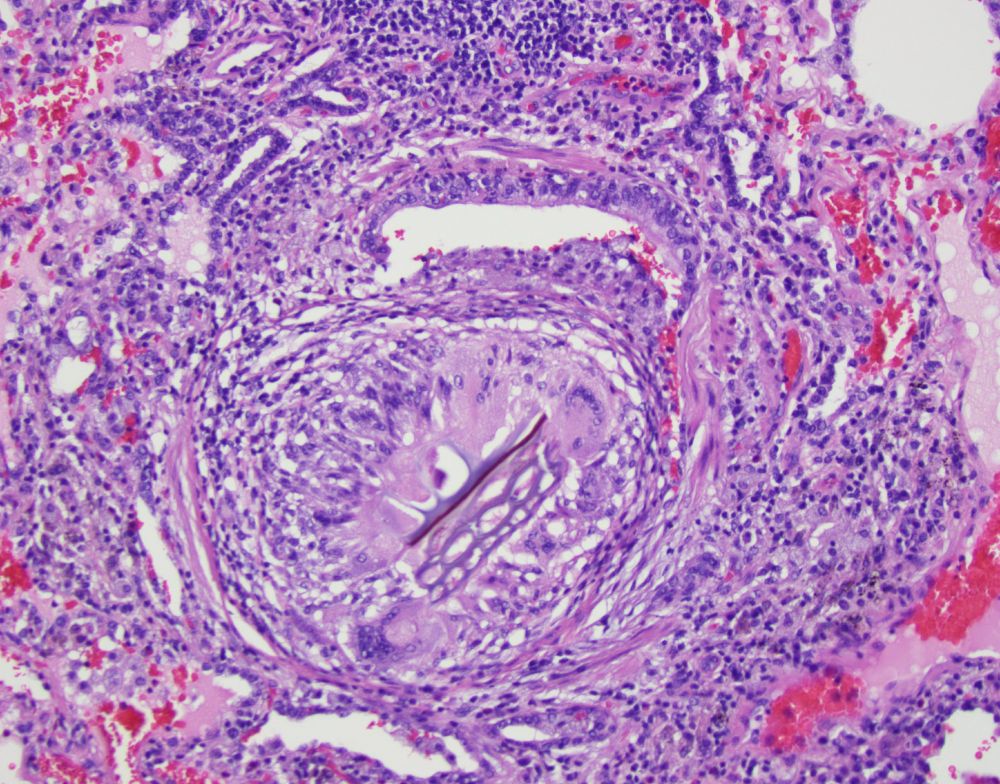

Granulomatous inflammation in lung due to aspiration of food particles #PathSky #LungPath #PulmSky @smlungpathguy.bsky.social